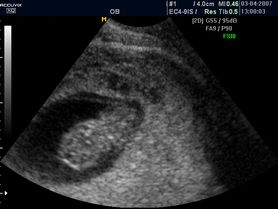

Płód w 8 tygodniu ciąży (zdjęcia)